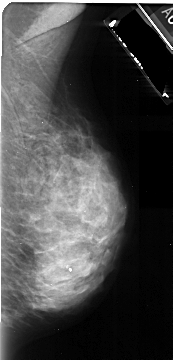

A_1043_1.LEFT_MLO

LEFT_MLO LINES 5326 PIXELS_PER_LINE 2746 BITS_PER_PIXEL 16 RESOLUTION 42 OVERLAY